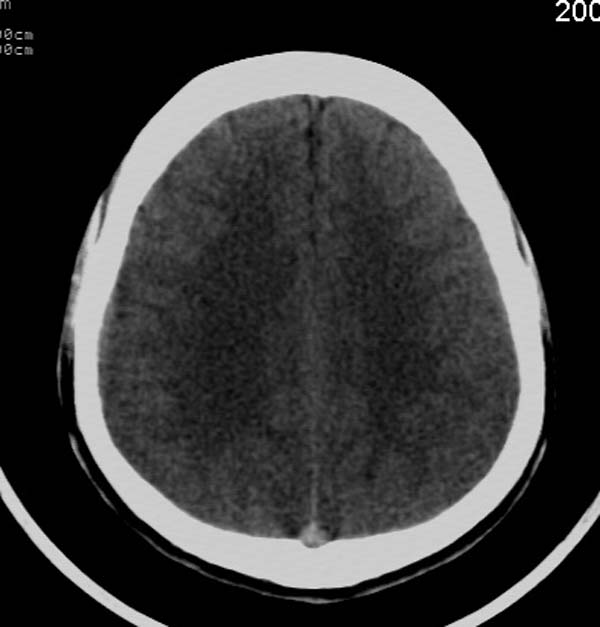

患者,男,24岁。头面部外伤后意识障碍1小时。

小脑幕缘密度增高,考虑有少量出血,建议复查

考虑右侧天幕缘少量蛛网膜下腔出血;建议:必要时复查。

支持少量蛛网膜下腔出血,建议复查.

考虑右侧天幕缘区域少量蛛网膜下腔出血。

报正常吧,短期复查